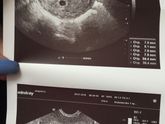

Была неделю назад на УЗИ, было два плодных яйца и вопрос до сих пор стоит, что одно может пропасть. Вчера начал очень болеть живот, схватками, как при месячных, на ночь взяла свечи, думала поможет, утром проснулась и живот все равно болел и так до сих … Читать далее

Что-то у меня совсем крыша начинает ехать. Все читаю всякое, боюсь, что ребёночек один останется (а любимый так обрадовался двоим) хоть ещё все под вопросом, но он говорит что ему два надо и хоть убейте, доволен как слон. В чем суть вопроса: по УЗИ сейчас … Читать далее